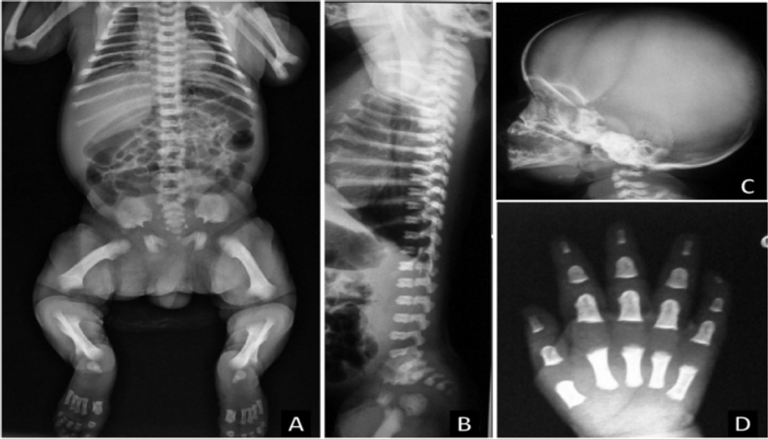

- الأشعة السينية (X-ray) لاكتشاف التغيرات الهيكلية في العظام، مثل قصر الأطراف، والتقوس في الساقين، وهي علامات مميزة للودانة.

- قصر القامة حيث يتراوح متوسط الطول في البالغين المصابين بالودانة حوالي 120 سم إلى 135 سم.

- حجم الرأس يكون كبيرًا نسبيًا مقارنة بالجسم، مع جبهة بارزة وجسر أنف منخفض.

- تكون الأطراف (الأذرع والأرجل) قصيرة بشكل غير متناسب مع الجذع، خاصةً في الجزء العلوي من الذراعين والفخذين.

- التقوس في الساقين، والذي يمكن أن يسبب مشاكل في المشي والوقوف.

- تكون الأيدي والأقدام قصيرة وممتلئة، ويكون هناك فراغ بين الإصبع الأوسط والبنصر.

- مشاكل في العمود الفقري مثل التقوس (الجنف) أو الحدب.